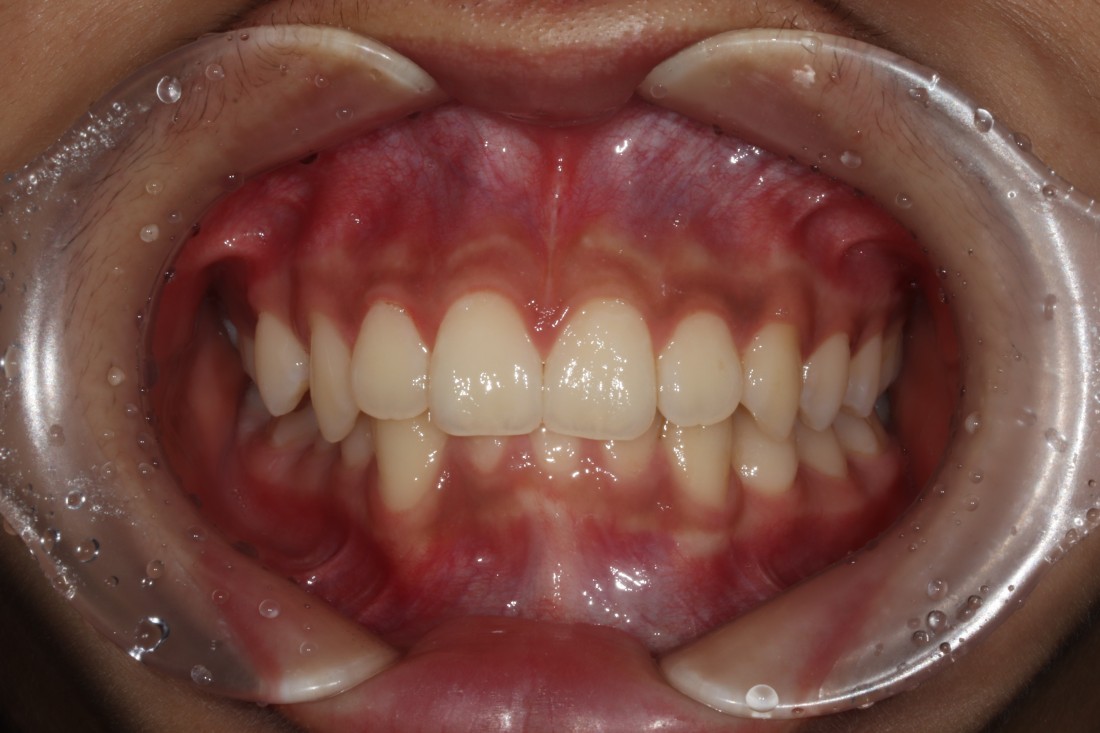

다양한 과개교합 교정 전/후 사진은

위의 사진을 클릭하시면 확인하실 수 있으며,

윗니에 아랫니가 거의 덮여있는

과개교합의 경우에는

턱관절 장애를 유발합니다.

윗니가 아랫니를 거의 덮어서

보이지 않을 정도의 부정교합의 종류인데요.